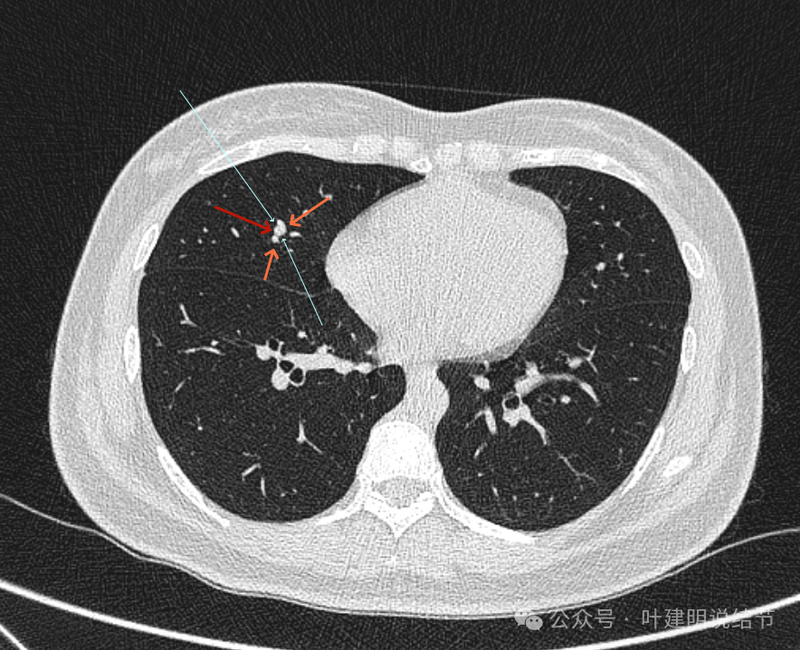

先看横断位的影像:

病灶出现,图上标注的桔色箭头所指的是肺血管;红色箭头所指的是病灶;天蓝色细线指的是血管与结节之间的间隙。病灶实性,与血管挨得近,但没有紧贴或侵犯。

病灶与血管间仍有低密度线状,血管在此处刚好分叉似的。

病灶有膨胀性,血管贴得近。

似乎见血管围着结节灶,两者紧贴,密度略有不同,导致上图中血管受压成细条状,病灶是软组织密度。

看着像靠心脏这一侧的半圈是血管受压形成的包膜似的,但靠胸肋侧没有血管,所以略偏白些的血管影在外侧见不见,外侧见到的是病灶的边缘,比较光滑,两者之间密度不同(天蓝色细线所指是两者分界,虽紧挨却密度不同)。